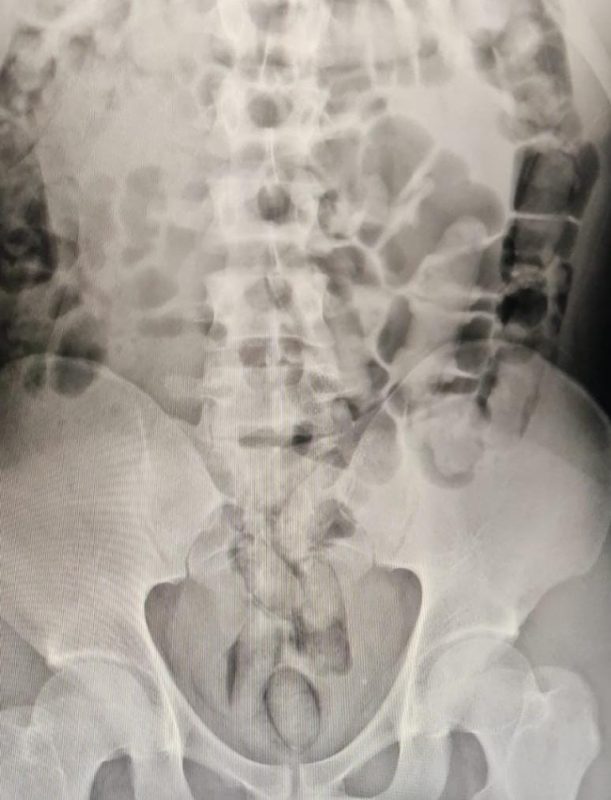

Um homem de 29 anos foi preso em flagrante com 29 cápsulas de drogas no estômago. O caso foi registrado pela Polícia Civil, na noite do domingo (18), em São Lourenço do Oeste, no Oeste de Santa Catarina. – Foto: Polícia Civil/Divulgação/ND

O suspeito passou por exame de raio-x, que confirmou a existência das cápsulas com cocaína. Ele cumpria pena no Presídio de Chapecó e estava em saída temporária de 7 dias. O caso segue sendo investigado pela Polícia Civil.